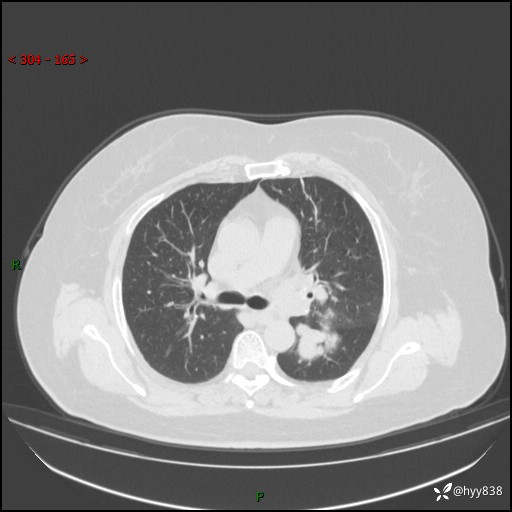

主诉:检查发现左上肺结节8年,较前增大。

简要病史:患者于8年前体检行胸部CT检查发现左上肺结节(4mm),患者平素间断咳嗽咳痰,无心慌、胸闷、胸痛、呼吸困难、低热、盗汗,无头痛、头晕,无腹痛、腹胀等不适,未行特殊处理,定期复查。2023-09-21胸部CT示左上肺结节(2cm)较前增大,2024-02-01胸部CT示左上肺尖后段(39*32mm),左侧肺门及纵隔淋巴结增大,现患者欲求手术治疗,遂来我院就诊,以“左上肺结节”收入我科。 患者自起病以来,精神可,睡眠可,饮食可,大小便正常,体重无明显改变。

胸部CT平扫